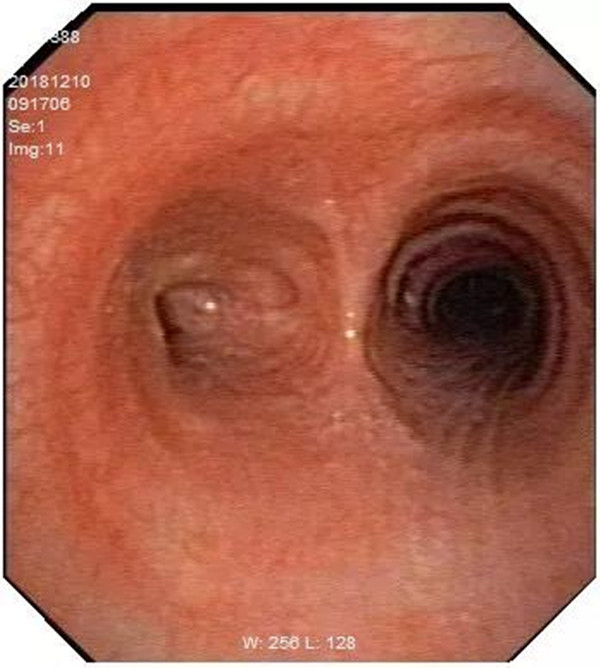

另外,支气管结核很容易导致气管支气管狭窄,在病情的发展过程中,这种狭窄还会有一定程度的加重,支气管狭窄甚至闭塞可能导致远端的肺组织萎陷并完全失去功能,严重的影响患者的生活质量。

我们做气管镜除了观察是否有支气管结核之外,还可以对病变的支气管采取镜下治疗,如气管内加药治疗、清除气管内痰液及坏死物,还可以用冷冻及球囊扩张等方法以减轻和改善气管狭窄闭塞的目的。